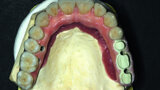

Fig. 20: Prosthetic work based on a model where veneering of the gum was started and with crowns.

Fig. 21: Openings for screws are located before placing the crowns.